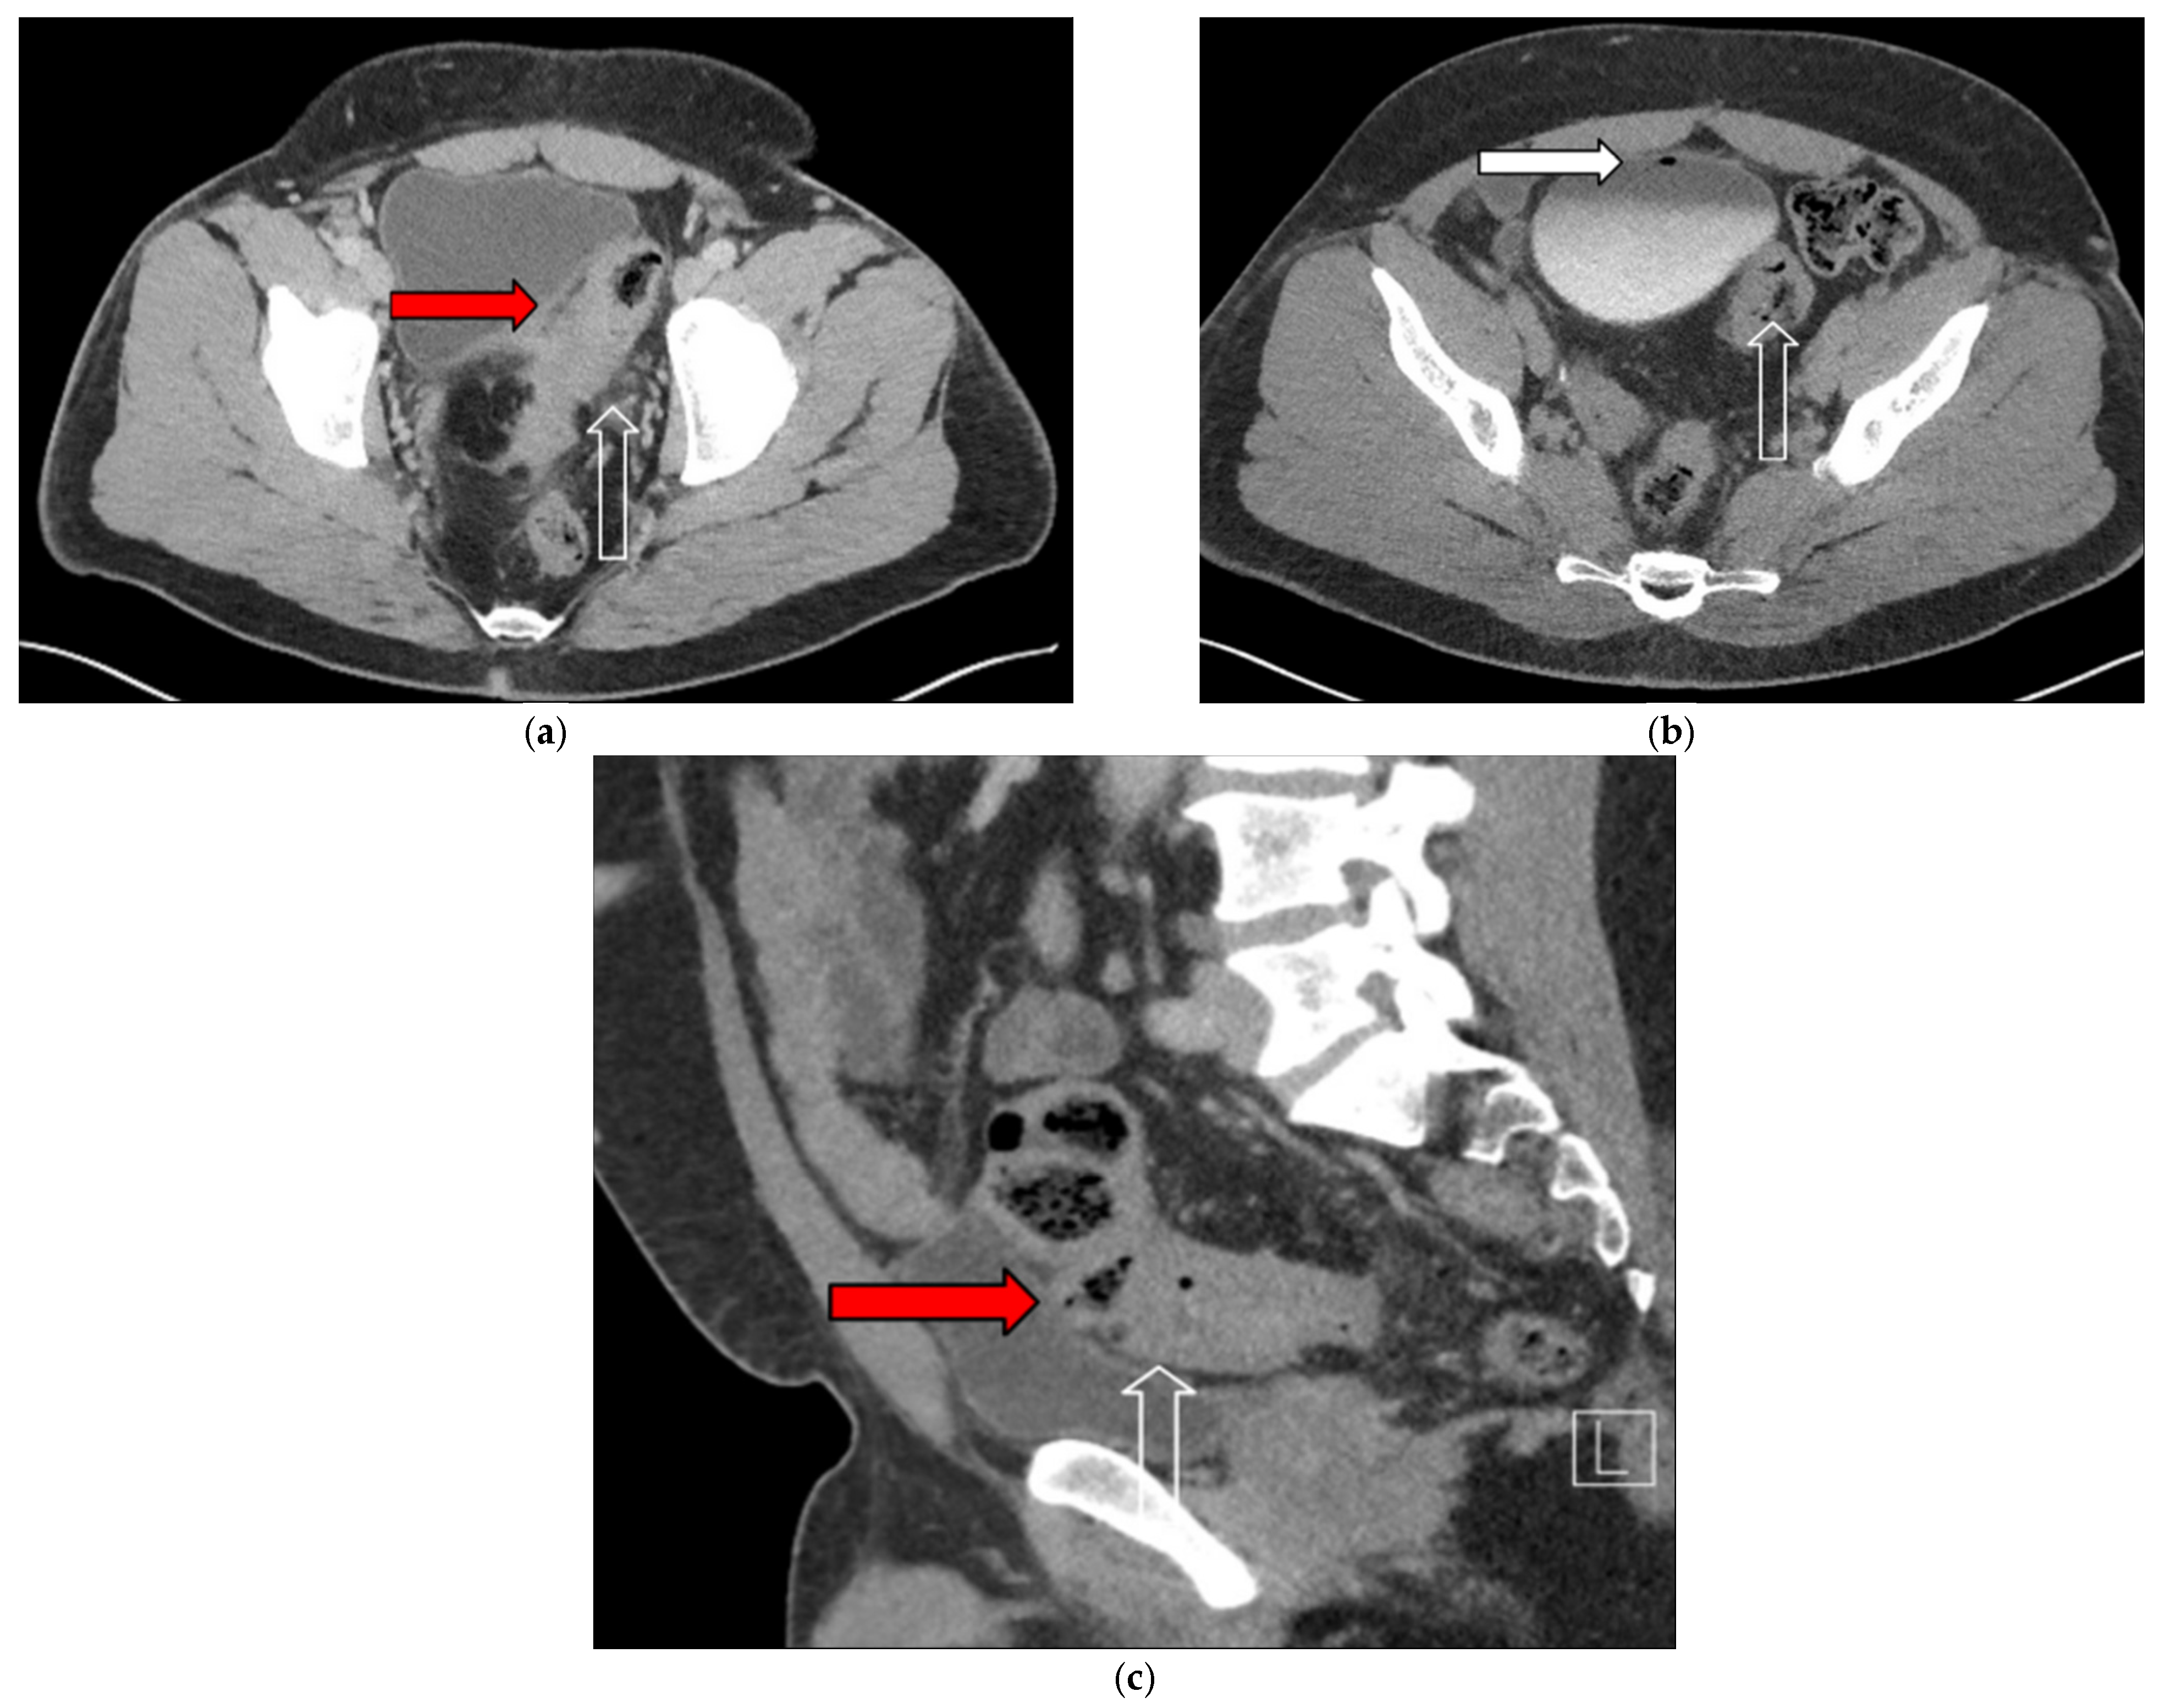

3.1. Case 1